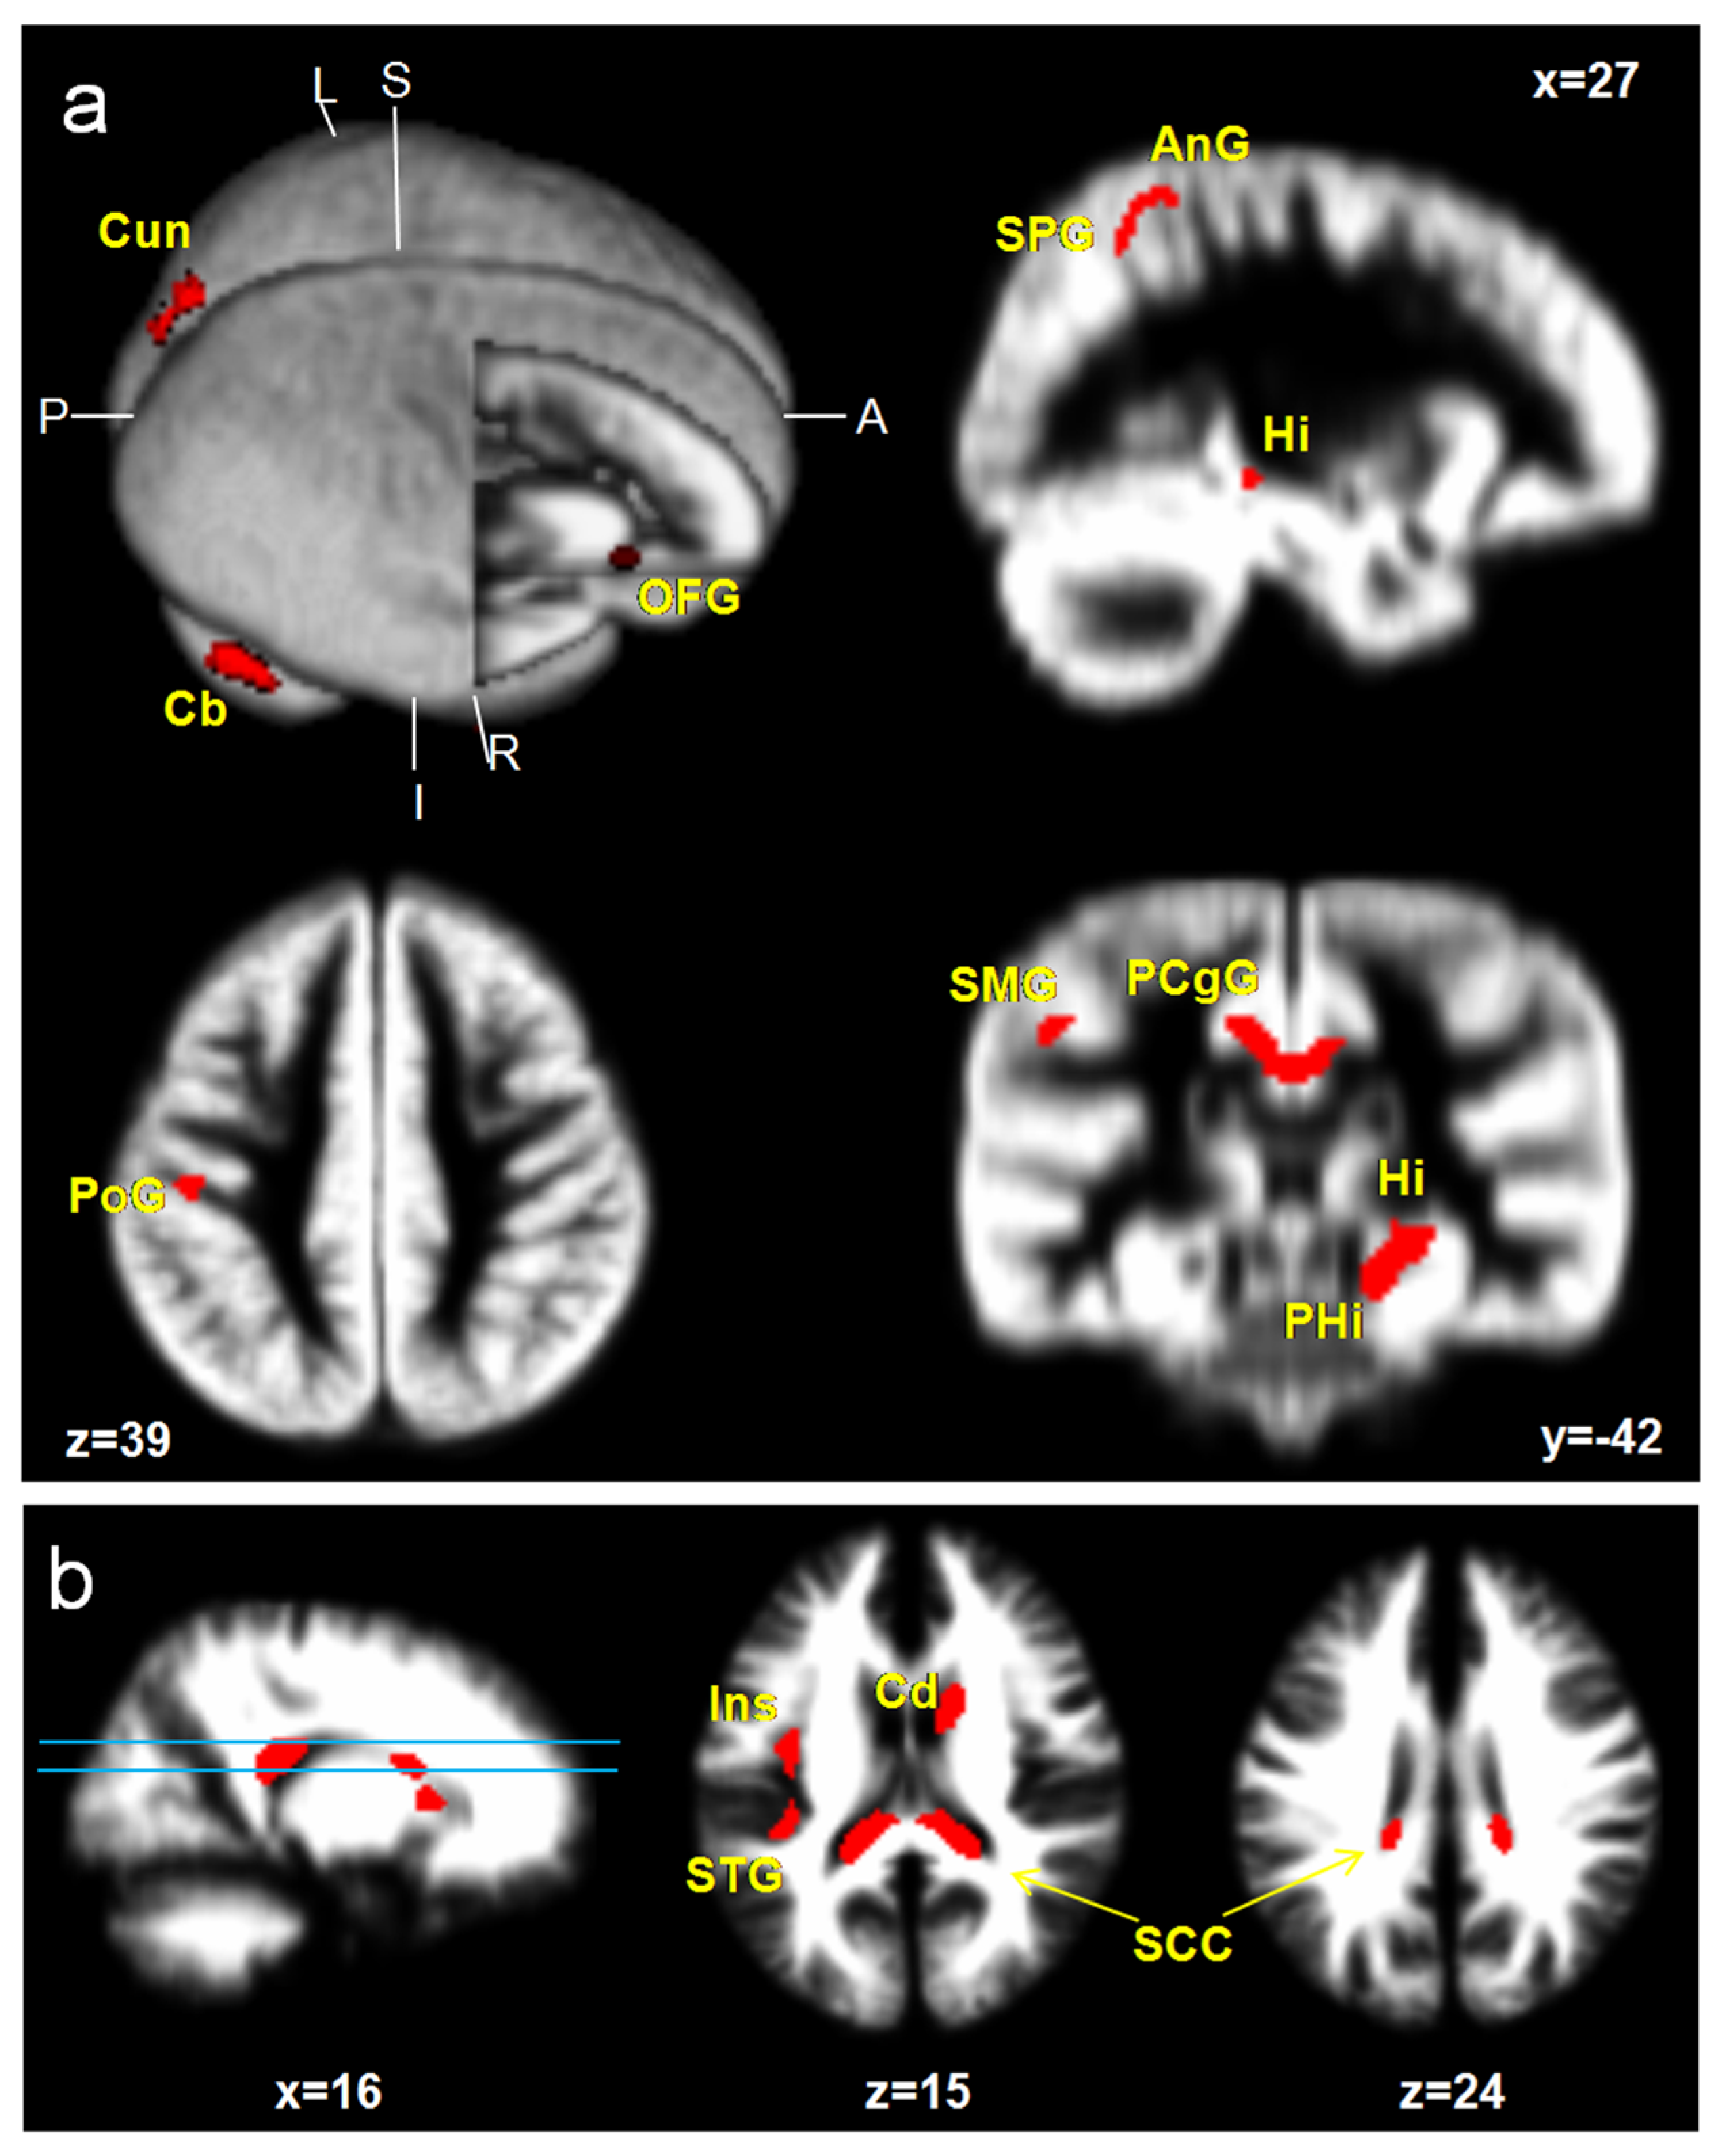

ICPP girls showed a significant increase in GM volumes; specifically, the medial prefrontal cortex (mPFC), superior parietal gyrus (SPG), supramarginal gyrus (SMG), angular gyrus (AnG), postcentral gyrus (PoG), superior occipital gyrus (SOG), cuneus (Cun), hippocampus (Hi), parahippocampal gyrus (PHG), posterior cingulate gyrus (PCgG), and cerebellar cortex (Cb) (uncorrected p < 0.001, excluded 100 voxels). However, reduced brain areas were not found in ICPP girls. Increased WM volumes are shown at the insula (Ins), caudate nucleus (Cd), and splenium of corpus callosum (SCC) (Figure 1, Table 2).

Figure 1.

Brain areas with a significant increase in GM (a) and WM (b) volumes in ICPP girls in contrast to age-matched healthy girls (uncorrected; p < 0.001, excluded 100 voxels). Hi, hippocampus; PHG, parahippocampal gyrus; PCgG, posterior cingulate gyrus; Cun, cuneus; PoG, postcentral gyrus; SCC, splenium of corpus callosum; mPFC, medial prefrontal cortex; Ang, angular gyrus; SMG, supramarginal gyrus; SPG, superior parietal gyrus; STG, superior temporal gyrus; Ins, insula; Cd, caudate nucleus; Cb, cerebellar cortex.

In this study, the brain’s developmental morphological changes and the influence of the LH on brain structure in ICPP girls were assessed by qualitative and quantitative analyses by using a VBM study based on the DARTEL algorithm and statistical approach. At first, two groups composed of ICPP girls (age 7 to 9) and the age- and sex-matched group were analyzed by a two-sample t-test (p < 0.001). The areas with increased GM in ICPP were the frontal lobe: mPFC; parietal lobe: SPG, SMG, AnG, and PoG; occipital lobe: SOG, and Cuneus; limbic system; Hi, PHG, and PCgG; cerebellum: Cb. The increased WM volumes were observed at Ins, Cd, and SCC. However, reduced WM areas were not observed. A longitudinal pediatric neuroimaging study [16] reported that the brain growth patterns across ages 4 to 22 show linear increases in WM, but in GM, they demonstrated quadratic forms in which there was increased GM in previous puberty followed by a decrease post-puberty. Specifically, the developmental curve of the frontal lobe and parietal lobe peaked at about 12 years old, while the developmental curve of the temporal lobe peaked at about 16 years old, while the GM of the occipital lobe continued to increase until the age of 20 years. Our results, specifically, the increased GM and WM volumes in ICPP girls over the age- and sex-matched group, suggest that brain development during PP showed a similar pattern to normal puberty. Thus, it is speculated that ICPP girls may be suffering an onset of synaptic proliferation and reorganization similar to puberty [16].